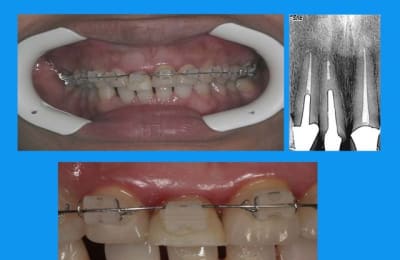

11 a du en passer par l'odf

curieux de voir que le dépassement a suivi la dent... serait un instrument cassé?

Dépassement dt5hca - Eugenol

non la patiente détestait ses diastèmes inf(microdontie relative des inc)

l'IC est scellé definitivement au fuji+

la provisoire au durelon (liquide thin)

traction en 3 mois

normalement la contention doit être laissée en place 3 mois minimum

cela dit ds ce cas,un ttt odf pr les incisives du bas ayant été entrepris,elle est restée plus longtemps

pr repondre à noa... ce n'est pas moi qui fais l'odf,je me suis contentée de demander,puis de travailler en parrallèle et de concert

l'odf a utilisé un arc 0.014 thermique ,force constante faible

la dent provisoire a été meulée au fur et à mesure de la traction = 3mm

elle a un sourire très gingival et des prothèses déjà en place:la chir de 3 à 3 aurait été plus rapide mais peut être moins esthetique... et je n'ai pas osé....

la patiente a en bouche des ceramiques faites depuis plus de 15 ans(made in USA)avec les traitements s'y référents

seule la 11 a cassée(due au deplacement de l'antagoniste? peut être,sans doute)

je ne me suis pas acharnée à retirer le cône noyé ds la pâte(acryl? ou thermafill mais cela existait il à l'epoque?) vu l'absence d'image apicale et.... le fait que je n'y suis pas arrivée:)

tort? raison?

on verra mais à un an 1/2(IC et prov posés en nov 2005) pas gd chose ne se passe